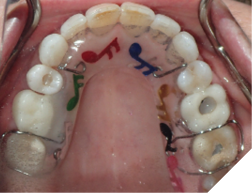

4. Bonded permanent retainer (Fig. 11AB)

Checking for:

i. smooth edges

ii. intact wire

iii. sufficient composite resin amount on bonded teeth

iv. showing good stability when checked with a hand instrument

Fig. 11A

Fig. 11B

Fig. 11C

Fig. 11D